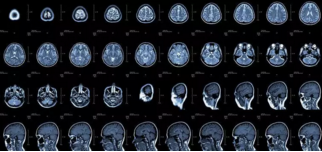

核磁共振

搖一搖再看

4.png

核磁共振機(jī)使用較強(qiáng)大的磁場,使人體中所有水分子磁場的磁力線方向一致,這時(shí)磁共振機(jī)的磁場突然消失,身體中水分子的磁力線方向,突然恢復(fù)到原來隨意排列的 狀態(tài)。簡單說,就相當(dāng)于用手搖一搖,讓水分子振動(dòng)起來,再平靜下來,感受一下里面的振動(dòng)。所以,核磁共振也被戲說為是搖搖看的檢查。